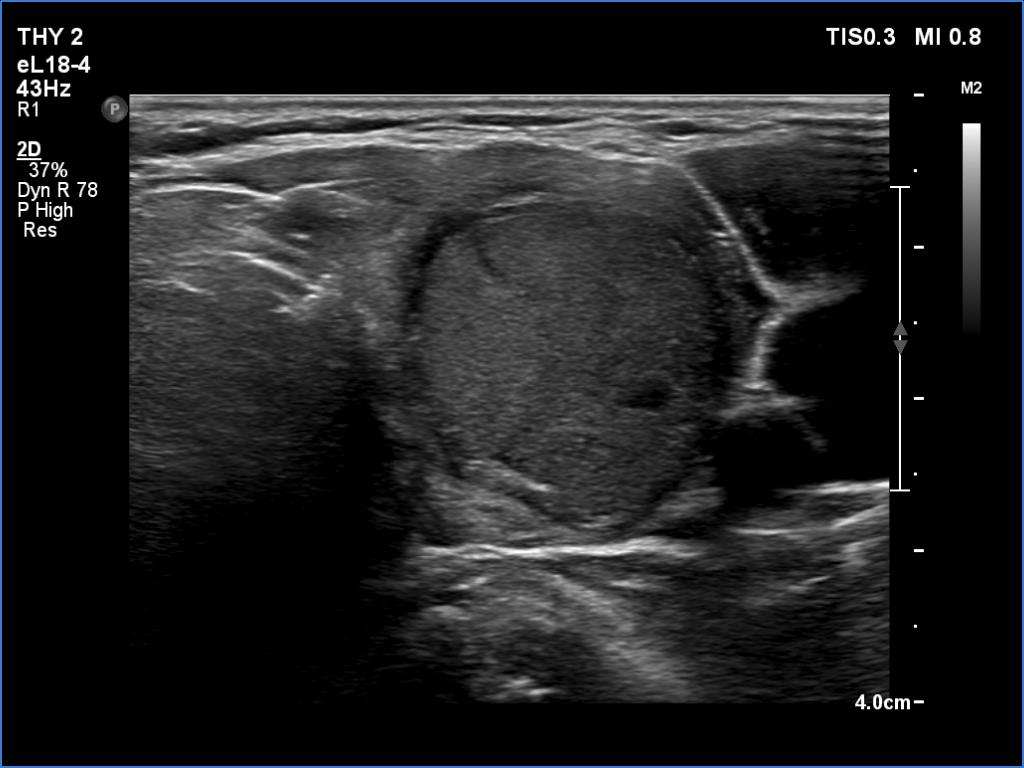

Clinical presentation: A 66-year-old woman was referred for cytology. The patient felt discomfort in her neck while lying on her left side for a few months.

Palpation: a firm nodule in the left lobe.

Cytology resulted in atypical follicular tumor.

Diagnosis: Hashimoto's thyroiditis. Suspicion of follicular cancer.

Suggestion: left lobectomy and frozen section during the surgery.

Frozen section disclosed follicular cancer, therefore total thyroidectomy was performed. The definitive histopathological diagnosis was widely invasive follicular cancer and Hashimoto's thyroiditis.